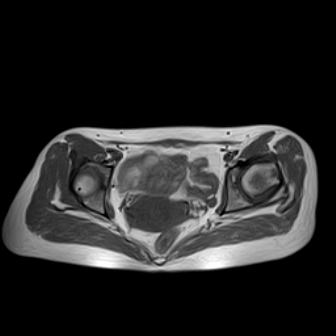

请看看我的片子,我得的什么病,该怎么治疗?谢谢[img][/img]

片子不全,应该是左侧股骨头无菌坏死,右侧似乎没问题,到正规医院治疗,千万别看广告去小医院,吃中药什么的,都是骗人的(说了也白说,百分百都得让人骗点钱才甘心。)

应该是左侧股骨头无菌坏死